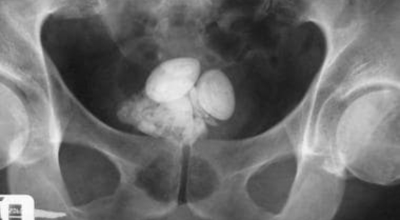

요로결석 증상 - 배뇨 이상 또는 배뇨통

방광 결석, 요도 결석은 소변 볼 때 심한 통증과 소변을 수시로 보거나 잔뇨감 과 같은 증상이 나타날 수 있어요. 요도 결석인 경우 심한 통증과 소변을 보지 못해 응급실을 가는 경우도 있답니다.

요로결석의 치료방법은 당연히 결석을 없애는 방법이 최우선인데요 체외충격파 쇄석술 이라고 하는 시술을 통해 결석을 자연 배출될 수 있도록 하는 방법이 있습니다. 충격파 장치에서 고에너지 충격파를 쬐어 결석을 파괴하면, 결석 조각이 알아서 배출될 수 있도록 하는 시술입니다.

입원이 필요치 않은 시술이며 시술 후 1시간이면 바로 일상 회복이 가능하다고 해요. 물론 더 심한 경우는 내시경 결석 제거술등의 수술을 통해 제거해야 하는 경우도 있답니다. 그렇기 때문에 요로결석 증상이 발생한 초기에 빠르게 대응하여 간단한 시술로 결석을 제거하는 것이 최우선입니다.